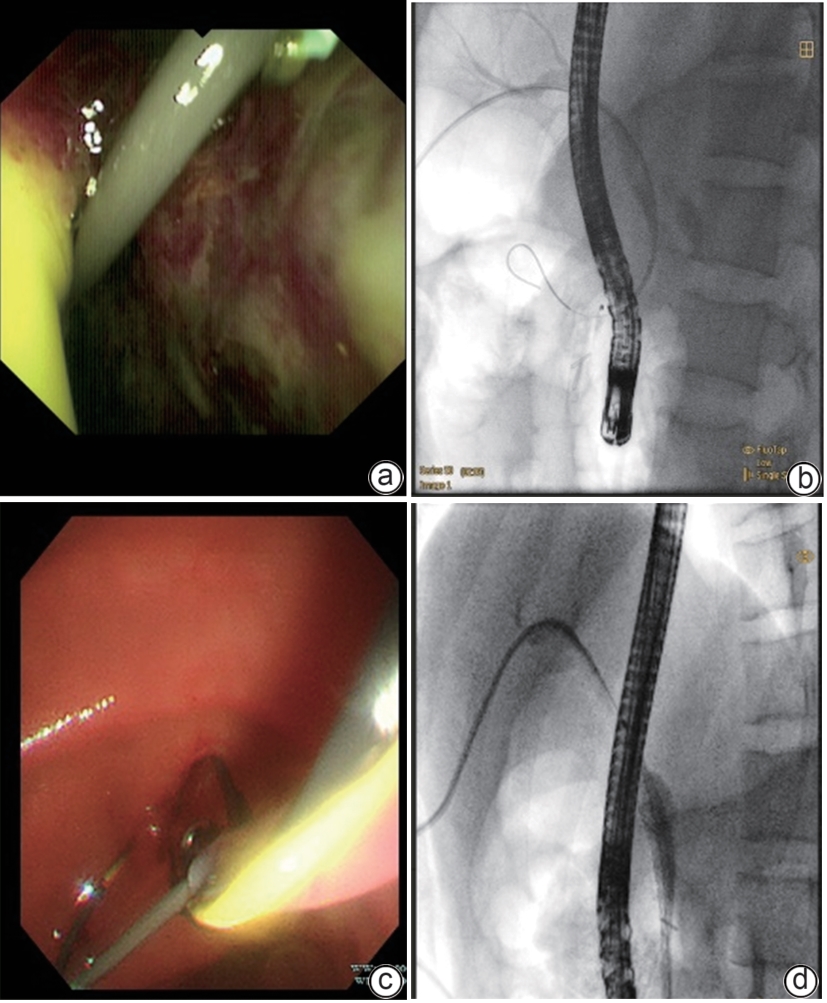

• Duodenum-preserving pancreatic head resection, also known as Beger surgery, has a high incidence rate of bile duct injury after surgery, while the treatment modality for bile duct injury depends on the severity of the injury, and endoscopic therapy is often challenging in case of severe bile duct injury. Recently a patient with biliary fistula after Beger surgery was admitted to Affiliated Hangzhou First People’s Hospital, Westlake University, and successful diagnosis and treatment were achieved through oral choledochoscopy-assisted percutaneous-endoscopic rendezvous technique.